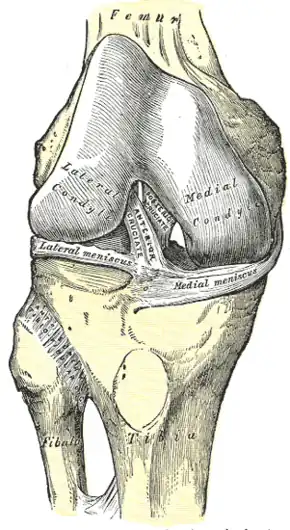

Right knee-joint, from the front, showing interior ligaments. Muscles of the back of the leg. Deep layer.

Muscles of the back of the leg. Deep layer.- Right knee in extension. Deep dissection. Posterior view.